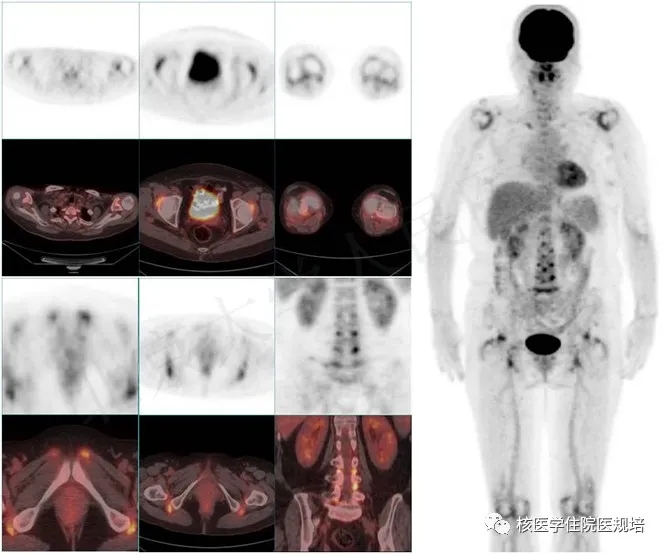

随着FDG PET/CT显像被引入感染与非感染性炎症的诊疗过程,人们发现PMRFDG PET/CT显像中通常显示出位于肩关节、胸锁关节、髋关节、坐骨结节和脊柱椎间关节等区域的滑膜炎性病变[3],这与具有类似临床表现的炎性肌病、结节性多动脉炎及ANCA相关性血管炎的PET/CT影像表现截然不同,但却可能与类风湿关节炎表现相似(图2)。然而,类风湿关节炎手部小关节为最常见受累部位,而PMR几乎无手部小关节受累情况,据此可用于两者的鉴别诊断,但前提是需对患者行全身图像采集,并将双上肢置于体侧,而仅行躯干部的图像采集无法全面观察全身关节受累情况。此外,需要注意的是,PMR患者容易伴发巨细胞性动脉炎,此时PET/CT可同时显示出具有大血管炎影像表现(图3)。有关巨细胞性动脉炎FDG PET/CT影像表现请参见本平台093号病例。PET/CT用于PMR鉴别诊断时还要注意密切结合临床资料,患者年龄通常在50岁以上;除多关节疼痛外,多伴有C反应蛋白和血沉的增高;PET/CT检查显示关节病变同时累及髋、脊柱及坐骨结节,手部小关节一般不受累,且除血管外无其他脏器组织受累。若符合上述临床及PET/CT影像特征,则诊断PMR的准确性可达90%以上,优于目前临床所用的分类诊断标准。

2.与风湿性多肌痛表现类似的风湿病PET/CT显像MIP图:A.类风湿关节炎;B.结节性多动脉炎;C.特发性炎性肌病;D.ANCA相关性血管炎

3. 风湿性多肌痛伴巨细胞动脉炎患者PET/CT显像MIP图(天津肿瘤医院提供)